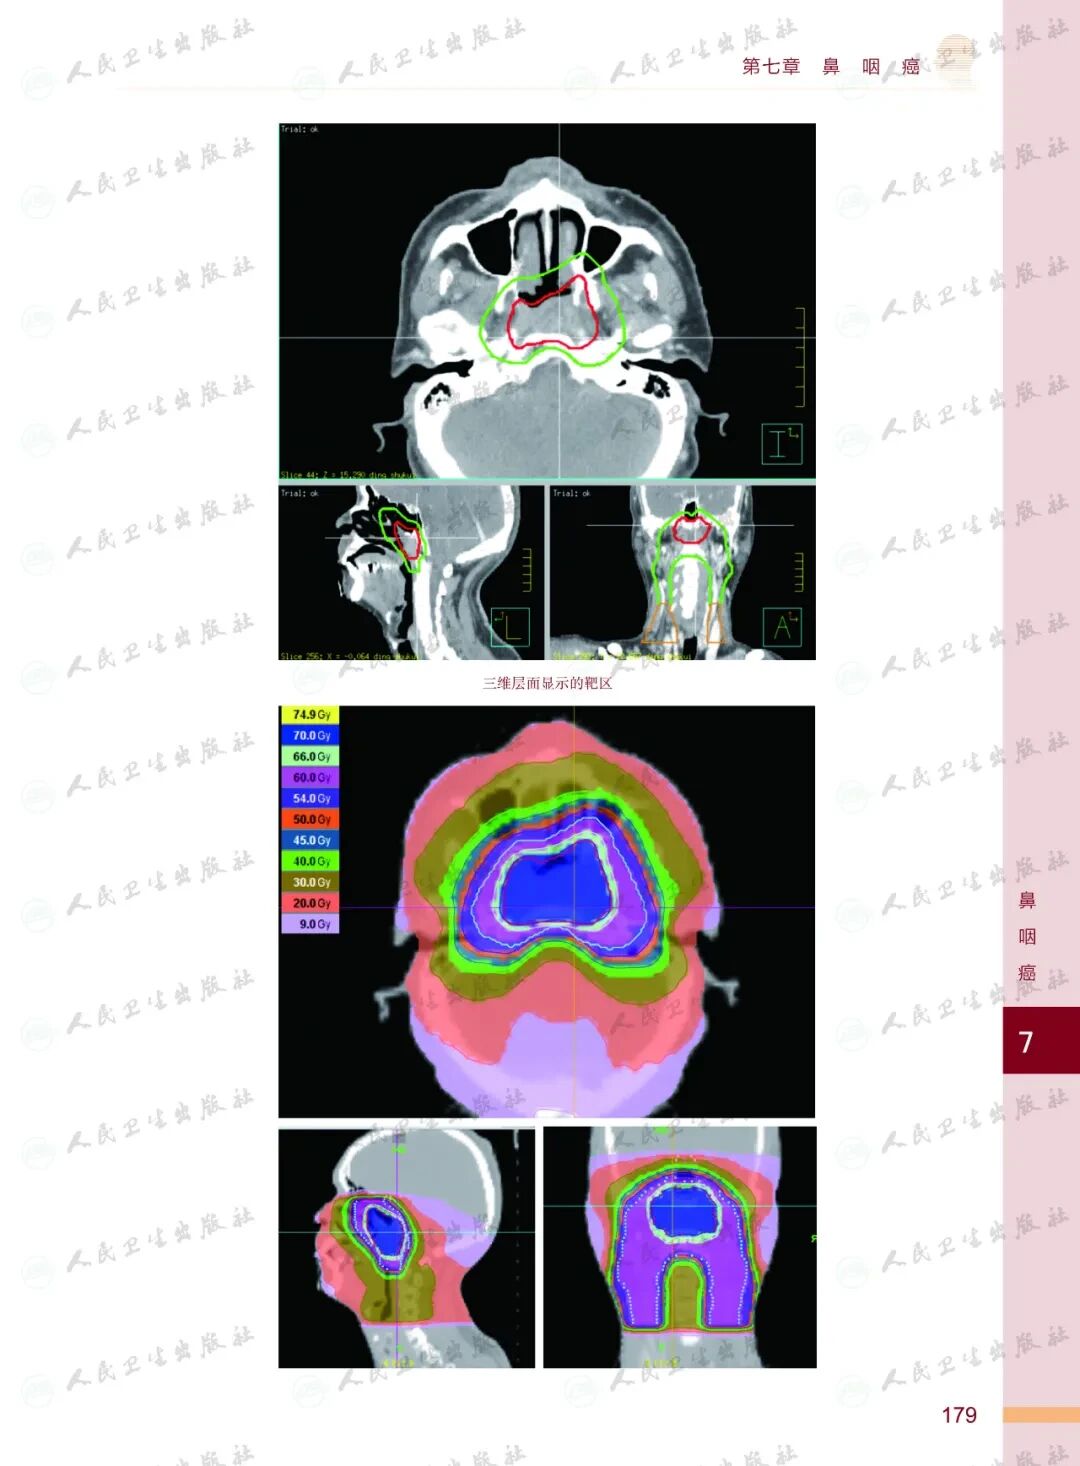

《头颈部肿瘤放射治疗图谱》

——不止是图谱,更是随唤随应的临床良师

样章试读